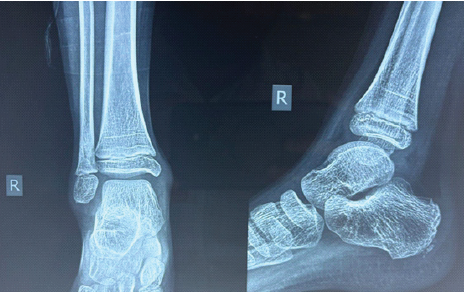

Bony biopsy, synovial biopsy samples sent for acid-fast bacilli (AFB) stain, tubercular cultures, and Cartridge-Based Nucleic Acid Amplification Test (CBNAAT) were all negative. The material that was sent for culture sensitivity grew P. aeruginosa. ATT was stopped. Culture-specific antibiotics for Pseudomonas were started. At present, around 10 months post-biopsy and drainage, he was walking without any pain and full weight bearing. X-rays at 10 months showed a healing lytic lesion of the fibula (Fig. 4). MRI showed resolution of synovitis: Joint effusion and marrow oedema (Fig. 5).

Figure 4: Plain radiograph of the ankle 10 months postoperatively showing the healing of a lytic lesion in the distal fibula.